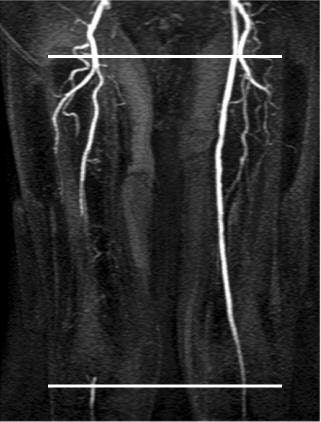

![]() |

| White lines indicate sites of cine phase contrast flow measurements. |

Results were derived from 96 arterial segments in 48 patients. Of the 96 segments, 26 were normal or mildly stenotic, 35 had moderate to severe stenosis, and 35 were occluded.